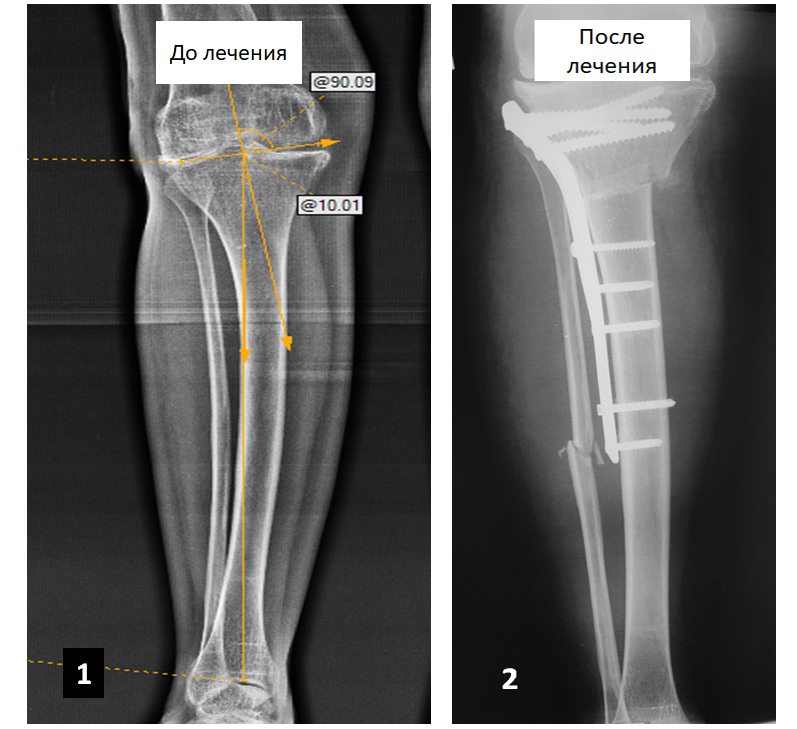

Мужчина обратился за помощью с жалобами на боли в области левой голени и левого коленного сустава. Во время консультаций в других медицинских учреждениях пациенту было предложено выполнить протезирование левого коленного сустава, от которого он отказался.

После проведения обследований была выявлена установочная варусная деформация левой голени и выполнена корригирующая резекция левой большеберцовой кости, в результате которой ось кости была восстановлена.

В настоящее время боли пациента не беспокоят, он полноценно пользуется конечностью в течение трех лет после операции.